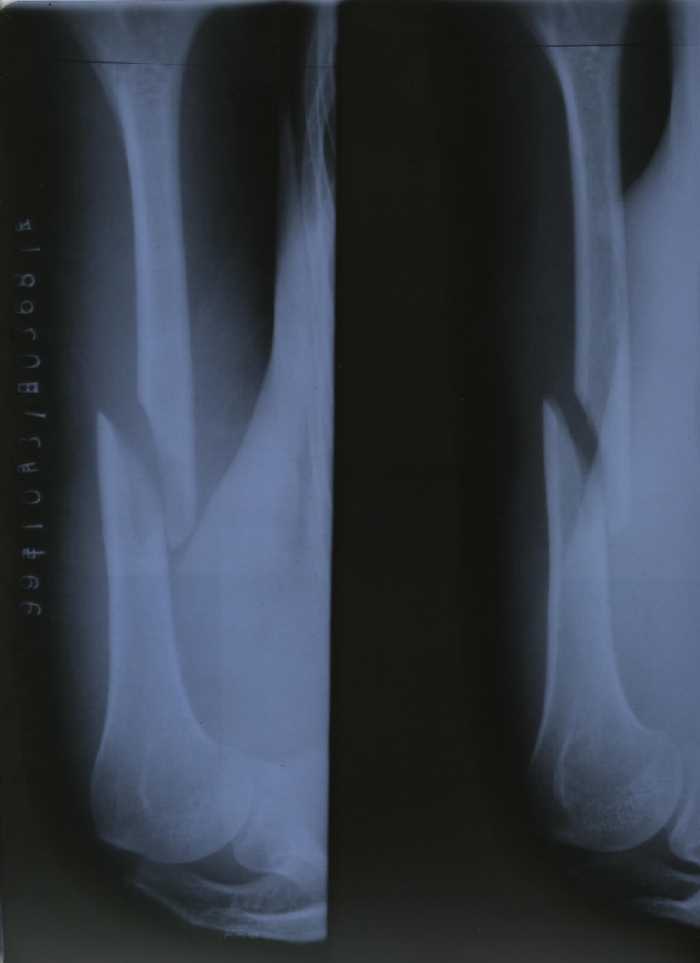

【明慧网1999年11月2日】 我是浙江省海盐县法轮大法弟子项进英,10月25日进京上访遭公安毒打,左胳膊肱骨骨折。

1999年10月25日,我们一行三人去天安门广场,准备上访。在广场被警察无故拦住盘问:是不是炼法轮功的。我们给予肯定的回答,就被带到附近的一个派出所,那里已经有五六十名大法弟子。登记时我们只回答自己是大法弟子。大家齐背“论语”。警察把十几人拖出,戴上手铐。(一手从肩膀下去,另一手从背后上来的那种很难受的铐法。)警察还让我们跪着,把头往墙上撞。在被铐住的情况下,一个警察还用力反复抻拉我的胳膊,听到胳臂“咔嚓”的一声,我疼得头上直冒冷汗,我知道这是自己的业力,默默忍受着。十五分钟左右,警察见我脸色不对,没有任何声响,就将我的手铐拿下,还晃晃胳膊看是不是装的,又怀疑是脱臼,装了几次但没装上。后来我们被卡车拉至北京城区的一个大院。从车上下来被审讯,然后又被送上车。审讯时一回答是大法弟子就遭毒打。我们被下车、审讯、上车两次。被脱衣服搜查后于10月26日一点左右送至看守所。检查时发现我的胳膊伤势严重。 26日早上一医生来查,当问我的名字我回答是大法弟子时,他就不看了。 27日带我去医院拍片:肱骨骨折,连医生都十分惊讶。30日上午又带我去医院拍片,几个医生会诊说要动大手术。我不愿意做手术,他们就用夹板把我的胳膊绑上,固定后再次拍片,因被强行矫正片子看似正常。警察将前后两张不同的片子均带回。当日下午又提审我, 让我回家,我被海盐公安局警察带回招待所。后找机会出去。现在全国云游。

1. 项进英左臂肱骨骨折后的X光检查结果

(注:从照片和X-ray片看,这位弟子遭打的胳膊应有小血管的破裂。)